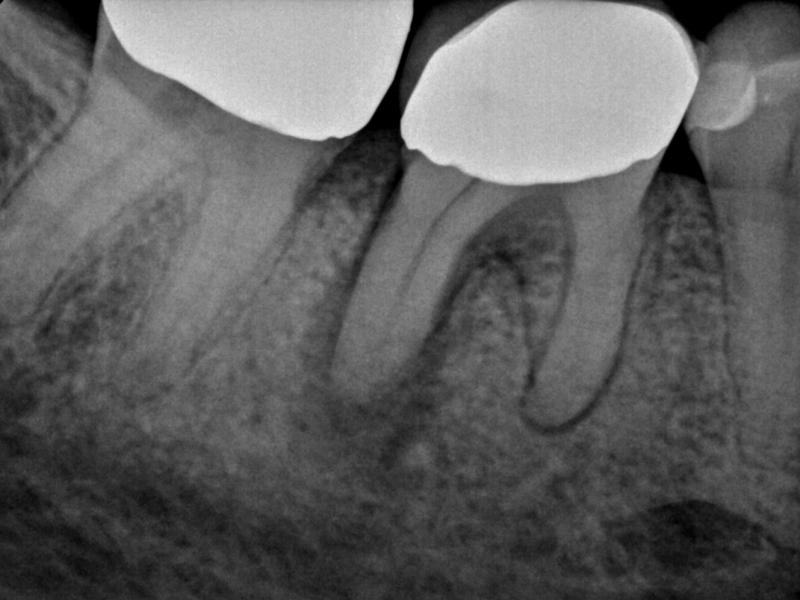

Guarded Pre-Op with Healing Evidence

Pre-Op